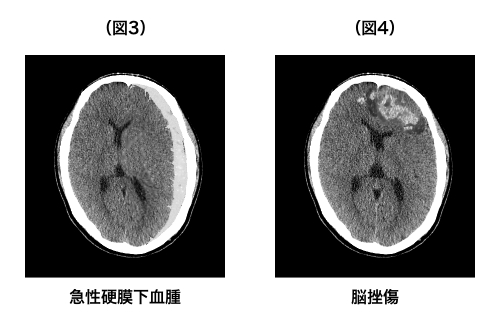

急性硬膜外血腫、急性硬膜下血腫、脳挫傷は頭部の外傷の直後に頭の中に急激に出血が起こるという点では同じですが、出血が起こる部位が異なります。硬膜という脳を包む膜の外側に出血が起これば急性硬膜外血腫(図2)、硬膜の下で脳よりも外側に起これば急性硬膜下血腫(図3)、脳そのものが傷ついて出血した場合は脳挫傷です(図4)。

※(図1)は正常なCTであり、院長自身を撮影したもの、他の出血の画像は(図1)を加工したものです。

※(図2)凸レンズ型の血腫が特徴的

※(図3)三日月型の血腫が特徴的

※(図4)脳の内部に白と黒が入り混じったような画像が特徴的